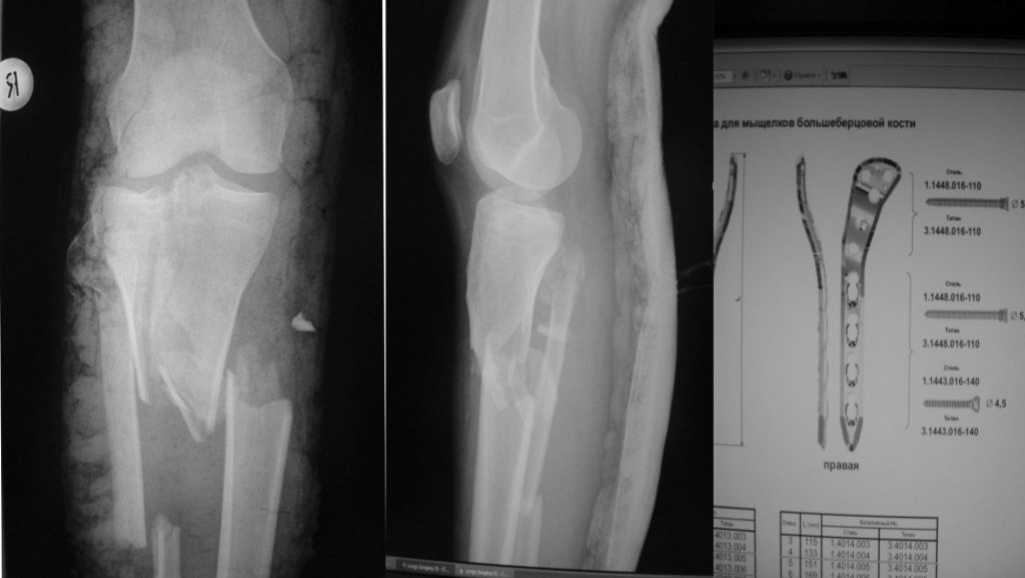

Закрытый перелом проксимального конца правой голени. (см снимки). Из сопутствующих: перелом правого луча в т.м. без смещения. ЗЧМТ. Ушиб головного мозга, субарахноидальное кровоизлияние. Левосторонний гемипарез. Неосложненный перелом 3-4 ребер справа. В настоящий момент состояние удовлетворительное, в сознании, адекватна, ориентирована. Гемипарез отстраивается. Сила руки почти полная. Сила ноги 3-4 балла. Динамика положительная. На КТ головного мозга: имеются множественные очаги ушиба мозга в правом полушарии. САК. Будьте любезны, подскажите, какой метод остеосинтеза и фискатор вы считаете оптимальным? Сроки выполнения операции? Я пока склоняюсь к открытому впралению без артротомии с артроскопическим видеоконтролем, остесинтез пластиной с угловой стабильностью ChM (см фото). При невозможности вправления суставной поверхности закрыто - артротомия. Как вариант - КДО аппаратом Илизарова